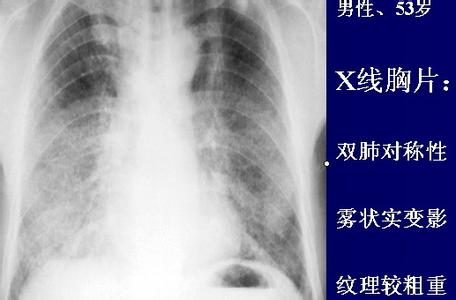

间质性肺炎x片,

间质性肺炎?急性心力衰竭?